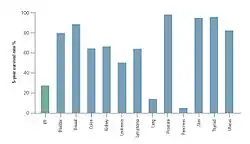

Aunque la FPI es una enfermedad rara, es la forma más común de todas las NII.[2] La prevalencia de la FPI se ha estimado entre 14,0 y 42,7 por cada 100.000 personas, sobre la base de un análisis de datos de reclamaciones sanitarias en los EE. UU. (la variación en los valores es debida a diferencias en las definiciones de los casos empleados en los análisis).[4][5] La FPI es mucho más común en hombres que en mujeres y normalmente se diagnostica en personas mayores de 50 años.[1]

La incidencia de la FPI resulta difícil de determinar ya que no se han aplicado, de manera constante, unos criterios diagnósticos uniformes.[1] Un estudio reciente en los Estados Unidos estimó una incidencia de 6,8-16,3 afectados por cada 100.000 habitantes. En los 27 países de la Unión Europea, diversas fuentes estiman una incidencia de 4,6–7,4 afectados por cada 100.000 habitantes,[6][7] lo que sugiere que unos 30.000–35.000 nuevos pacientes son diagnosticados con FPI cada año.[4][8]

Un reciente estudio observacional, retrospectivo de cohortes, en un único centro en el que se incluyeron pacientes con diagnóstico de NI en el Hospital Universitario de Aarhus (Dinamarca) entre 2003 y 2009 reveló una incidencia de 4,1 por 100.000 habitantes/año para la NI. La FPI fue el diagnóstico más común (28 %), seguida de la NI relacionada con conectivopatías (14 %), neumonitis por hipersensibilidad (7 %) y neumonía intersticial no específica (NINE) (7 %). La incidencia de la FPI fue de 1,3 por 100.000 habitantes/año.[9]

Debido a la heterogénea distribución de la afección por los diferentes países europeos, deben actualizarse los datos epidemiológicos mediante un registro pan europeo para la NI y la FPI.